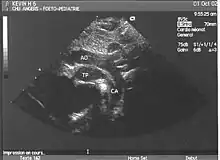

- L'échocardiographie qui est de plus en plus l'examen pratiqué en première intention. Cet examen permet d'affirmer le diagnostic en montrant les anomalies anatomiques, d'apprécier le caractère plus ou moins fonctionnel des shunts cardiaques fœtaux, de rechercher d'autres anomalies associées et dans une certaine mesure d'apprécier le retentissement de la malformation.

- Les coupes échographiques les plus utiles à cette fin sont :

- la coupe parasternale gauche grand axe : elle montre que le vaisseau issu du ventricule gauche (le plus postérieur) se dirige anormalement vers l'arrière et se bifurque précocement. C'est donc le tronc pulmonaire et non l'aorte comme normalement ;

- les coupes sous costales qui montrent bien le trajet parallèle des gros vaisseaux et leur inversion.